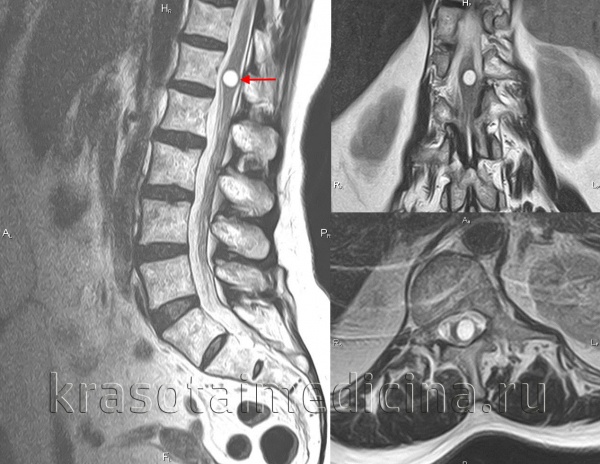

- экстрамедуллярные опухоли могут быть экстрадуральными (располагаются над твёрдой мозговой оболочкой) и интрадуральными, или субдуральными (локализуются под твёрдой мозговой оболочкой).

- менингиома (из клеток оболочек головного и спинного мозга);

- невринома (из клеток, образующих миелиновую оболочку нервов);

3. Магнитно-резонансная томография (МРТ) с контрастным усилением. На данный момент это основной метод диагностики новообразований спинного мозга. МРТ позволяет визуализировать весь спинной мозг и позвоночник и определить локализацию опухоли. Накопление контрастного вещества определяет не только распространение, но и гистологическую структуру опухоли [5] [6] .